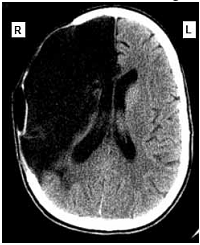

Uma mulher de sessenta e dois anos de idade foi levada pelo acompanhante ao atendimento médico de um hospital, às 7 horas e 30 minutos da manhã. O acompanhante relatou que a paciente tinha sofrido uma queda no banheiro de sua residência enquanto tomava banho, às 6 horas da manhã, e que ele a havia encontrado minutos depois. A paciente não conseguia mover o braço e a perna esquerdos, falava de forma lenta e arrastada, mas com sentido lógico. No exame clínico, foram observadas pressão arterial de 160 mmHg × 95 mmHg, ausculta cardíaca com ritmo cardíaco irregularmente irregular e frequência cardíaca de 98 bpm, sem sopros. A paciente estava com lentidão para responder a questionamentos, apresentava pupilas isocóricas e fotorreagentes, diminuição da sensibilidade dolorosa no lado esquerdo da face, paralisia facial central, hemiparesia flácida do hemicorpo esquerdo (mais acentuada nos membros superiores), reflexos profundos mais acentuados à esquerda e sinal de Babinski à esquerda. No eletrocardiograma realizado foram detectados ritmo de fibrilação atrial, com frequência ventricular média de 100 spm, SÂQRS = -30º, sinais de sobrecarga ventricular esquerda e alterações difusas e secundárias da repolarização ventricular. A tomografia computadorizada do crânio, sem contraste, realizada na paciente, apresentou o resultado mostrado a seguir.

O diagnóstico principal dessa paciente é de acidente vascular cerebral do tipo isquêmico.